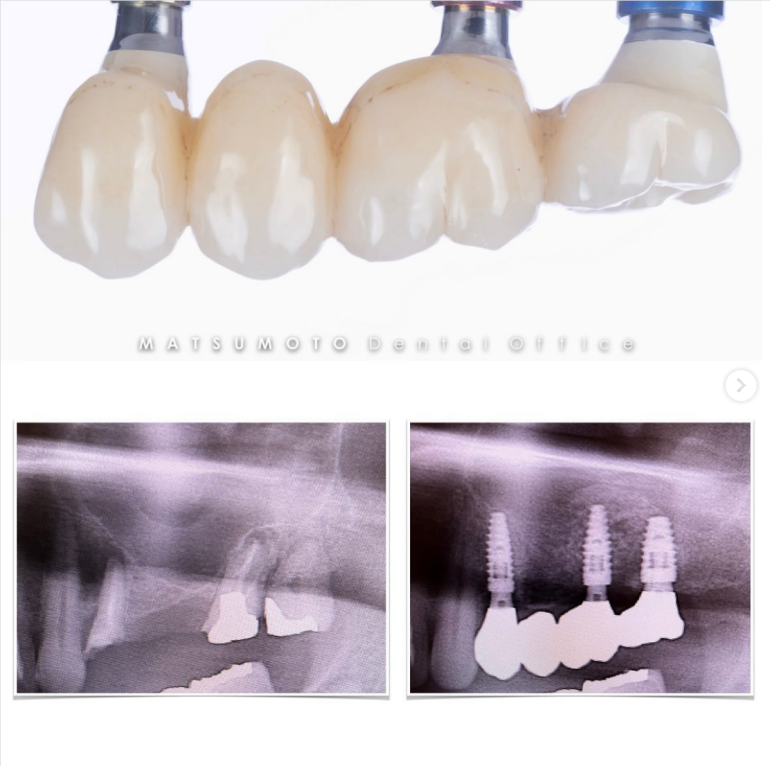

症例紹介27:インプラント治療/下顎6本《70代男性》

保存不可能なインプラントを抜去して、新しいインプラントを入れ変えました。

インプラントが良い位置に入ってることにより、安定した予後が期待できます。

インプラントガイドを使用することによってこのような結果を出すことができます。

上顎:インプラントが不適切な位置に入っており、仮歯を無理やり入れている状態。

下顎:インプラント周囲の骨がなくなっており、保村不可能な状態。

上顎:インプラントは保存できる状態。

下顎:インプラントを含め全て保存不可能な状態。

All-on-6を終えて

上顎:ロケーターアバットによる義歯

下顎:フルジルコニアブリッジ

治療期間:約半年

治療費:¥3,850,000(税込)

リスク:インプラントのネジが緩むことはありますが、なるべく連結しないような設計にしているので、問題をはやく見つけやすくしております。